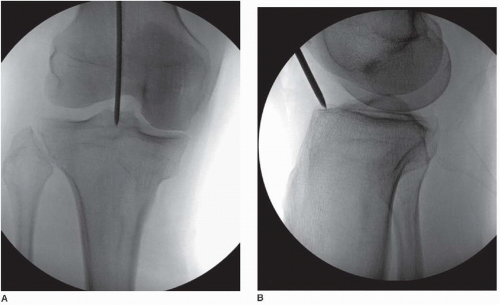

2. Entry point considerations in IM nailing of tibia

- Ideal: Centered just medial to the lateral tibial spine in the AP view, and at the anterior edge of the tibial plateau in the lateral view.

- Too lateral: Can cause eccentric reaming, cortical perforation, or asymmetric loading → increased fracture propagation risk.

- Too distal: Leads to posterior nail trajectory, increasing risk of fracture at the entry site or difficulty seating the nail.

In OI:

- The tolerance for even small deviations is reduced because the cortex is so thin and brittle.

- A lateral/distal start point increases hoop stresses during insertion → splits can propagate easily.